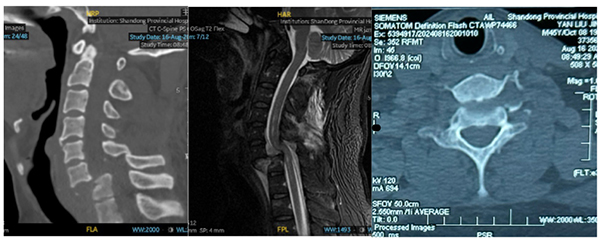

今年45岁的闫先生(化名)工作时意外被重物砸伤颈部,致使脖子剧烈疼痛、不能活动,双上肢麻木。在当地医院就诊,行影像学检查显示颈椎完全脱位,建议转诊至上级医院治疗。患者急诊转入我院,给予颈托制动,CT及MR显示:颈椎完全脱位,C6椎体向前明显移位、与C7椎体明显脱离;C7椎体压缩性骨折并椎管变形、颈髓损伤MRI表现。

创伤中心李连欣主任主持病例讨论,专家团队认为,患者治疗难度极大,并发症极高,治疗需要分期进行,在争取实现复位固定颈椎的同时,需保留足够的颈椎活动度,让患者拥有更好的生活质量。根据讨论方案,团队决定早期采取颅骨牵引,尝试通过牵拉恢复颈椎正常序列,也为进一步的手术创造条件。然而,经过2周的颅骨持续牵引,患者复查颈椎CT显示,颈椎脱位无明显改善,考虑颈椎双侧关节突绞索,继续牵引达到复位的可能性小。经过全科讨论,大家一致认为:一期手术采用后方入路,解除关节突绞索,恢复颈椎正常序列,同时彻底减压椎管;二期手术采用前方入路,进行C6/C7椎间盘摘除椎间融合,增强颈椎稳定性。